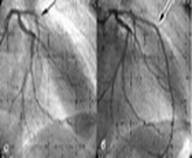

Коронарография является признанным "золотым стандартом" для выявления или исключения коронарной болезни сердца. Она позволяет определить выраженность сужения коронарных артерий, его локализацию и количество значительно стенозированных коронарных артерий (критерием такого сужения считается уменьшение площади просвета более чем на 70%)

В 30-х годах прошедшего столетия Вернер Форсман (Werner Forssman) Курнанд и Ричардс (Cournand and Richards) стали впервые использовать катетеризацию сердца как метод диагностики заболеваний сердца, что было революционным шагом, определившим перспективы и направления развития медицины на несколько десятилетий вперед, стало возможным выполнение инвазивного исследования сосудов, позволившее получить их прижизненную визуализацию. В 1958 г.произведена первая прижизненная селективная коронарная ангиография в клинике г. Кливленда (США). Она получилась случайно, когда во время катетеризации сердца у пациента с пороком аортального клапана катетер вместо прохождения через клапан попал в правую коронарную артерию пациента. Доктор Мэйсон Соунс — детский кардиолог, проводивший это исследование, с ужасом ожидал фибрилляции сердца, пока в течение 30 секунд контрастное вещество заполняло коронарную артерию. Но когда этого не произошло, д-р Соунс понял, что коронарные артерии можно прижизненно контрастировать без угрозы для жизни пациента. Впоследствии Мэйсон Соунс вспоминал: «Той ночью я понял, что, наконец, найден диагностический метод, определяющий анатомический субстрат болезни коронарных артерий». Его творческая работа стала крупным достижением, впервые позволившим устанавливать точный диагноз болезни коронарных артерий и заложившим основу для последующих операций реваскуляризации миокарда: сначала для коронарного шунтирования, а позднее – для коронарной ангиопластики. В 1967 г. Мелвин Джадкинс (Dr. Melvin Judkins модифицировал методику коронарной ангиографии по сравнению с использовавшейся техникой Соунса. Он стал вводить катетер через чрескожный прокол бедренной артерии чуть ниже паха, в то время как Соунс выполнял более сложную и травматичную процедуру введения катетера на руке через хирургически раскрытую плечевую артерию. Применение этой методики ограничено у больных с одновременным поражением атеросклерозом бедренных артерий, а также в случаях аномального расположения коронарных артерий. В этих случаях показано применение методики Соунса, которая предполагает введение катетера через обнаженную правую плечевую артерию.

Премедикация не обязательна. Накануне КАГ отменяют прием лекарственных препаратов, особенно В-адреноблокаторов. После введения катетера в артериальное русло одномоментно вводят 5000 ЕД гепарина. Все этапы катетеризации венечных артерий и их контрастирование проводят под постоянным электрокардиографическим контролем при периодическом определении давления в сосудах. В левую венечную артерию ренгеноконтрастное вещество вводят в количестве 4—6 мл со скоростью 4 мл/с, в правую артерию 3—4 мл со скоростью 3 мл/с. Исследования выполняют в нескольких проекциях. КАГ. всегда сочетают с катетеризацией левого желудочка и вентрикулографией.

Среди осложнений встречаются тромбоэмболии, кровотечения из места пункции сосуда и образование ложных аневризм, которые чаще наблюдаются у больных с выраженной сердечной недостаточностью, артериальной гипертензией, с нестабильной стенокардией, при аритмиях. В 0,33% случаев развивается острый инфаркт миокарда, в 0,9% — фибрилляция желудочков. Смертельные исходы составляют 0,24%. В хорошо оборудованной ангиографической лаборатории, где обследование проводит опытный врач, риск для жизни меньше, чем 0,1% (то есть смертельный исход менее 1 на 1000 обследований). Самое низкое число осложнений от коронарографии регистрируется в тех учреждениях, где в течение года выполняется не менее 200 обследований. При тяжелой стенокардии со слабой функцией левого желудочка у пожилых людей опасность смертельного исхода во время коронарографии возрастает до 1%.